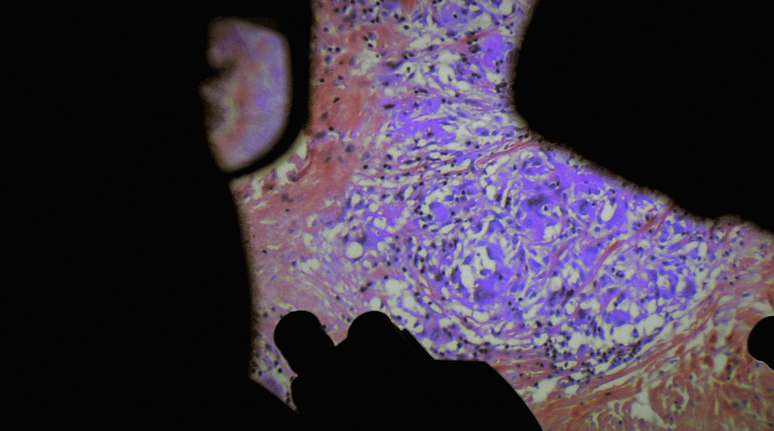

Quando se trata do gênero "horror corporal", pensamos principalmente em David Cronenberg, em filmes como A Mosca (1986) ou, mais recentemente, Crimes do Futuro (2022), que derivam seu horror da modificação ou manipulação do corpo humano. Mas se pudéssemos ver como é por dentro - literalmente - então só isso já seria horror corporal suficiente: não à toa que muitos não suportam a visão de sangue.

Nenhum outro filme nos últimos anos confrontou seu público de forma tão implacável quanto De Humani Corporis Fabrica (traduzindo, do latim: A Fábrica do Corpo Humano) - que, porém, não é um filme de terror, mas um documentário! No entanto (ou melhor: justamente por isso) o filme é uma verdadeira prova de coragem...

Lucien Castaing-Taylor e Véréna Paravel realizaram alguns dos documentários mais radicais dos últimos anos. Leviathan (2012), filme sobre a indústria pesqueira norte-americana, foi uma experiência audiovisual que ofereceu imagens inéditas, em Caniba (2017) os cineastas deixaram o assassino e canibal japonês Issei Sagawa fazer seu relato (movendo a câmera para milímetros perto de seu rosto e corpo). De Humani Corporis Fabrica é a sua mais recente obra - e transporta-nos para um lugar onde o horror corporal faz parte do quotidiano: o hospital.

De Humani Corporis Fabrica descreve o trabalho cotidiano em um hospital parisiense e, claro, consiste em grande parte em doenças, sofrimento e operações. Castaing-Taylor e Paravel vão aonde dói e forçam seus espect…